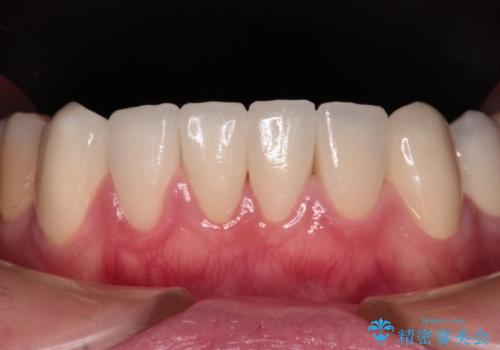

むし歯だらけの前歯をオールセラミッククラウンできれいに

全顎的にむし歯が多く、根管治療の必要奥歯や、審美的に気になっている前歯を中心にオールセラミッククラウンにて補綴治療を行うこととしました。

歯肉移植術による根面被覆を行うかどうかは非常に悩まれていましたが、歯肉が覆われたことで長く見えていた歯の長さが整い、きれいな前歯の仕上がりとなりました。